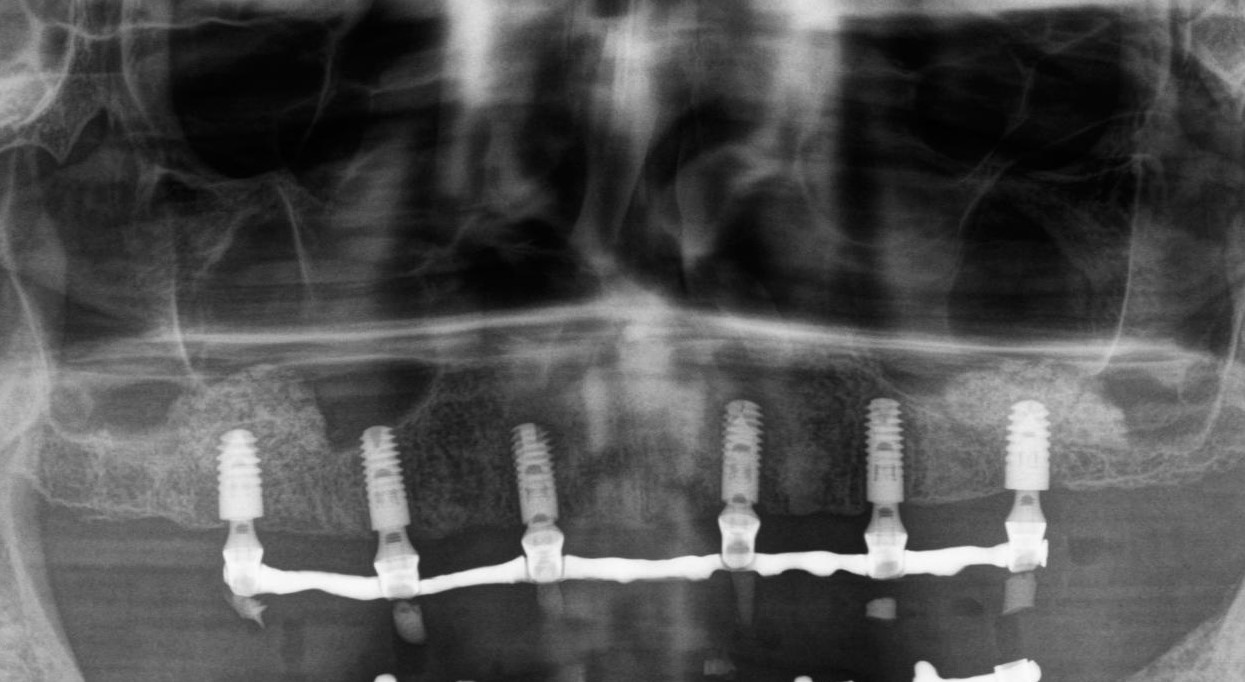

Дальше — хуже. Допустим, вы видите инстаграме обалденно сделанную работу по методике «все-на-шести» (это когда удаляются все зубы, устанавливается шесть имплантов, и сразу на них устанавливается временный, а иногда и постоянный зубной протез). Типа, «зубы за один день» — вот пациент совсем без зубов, а вот пролистнули — и он уже скалится своей новой голливудской улыбкой. Красиво, и на первый взгляд, очень показательно, правда?